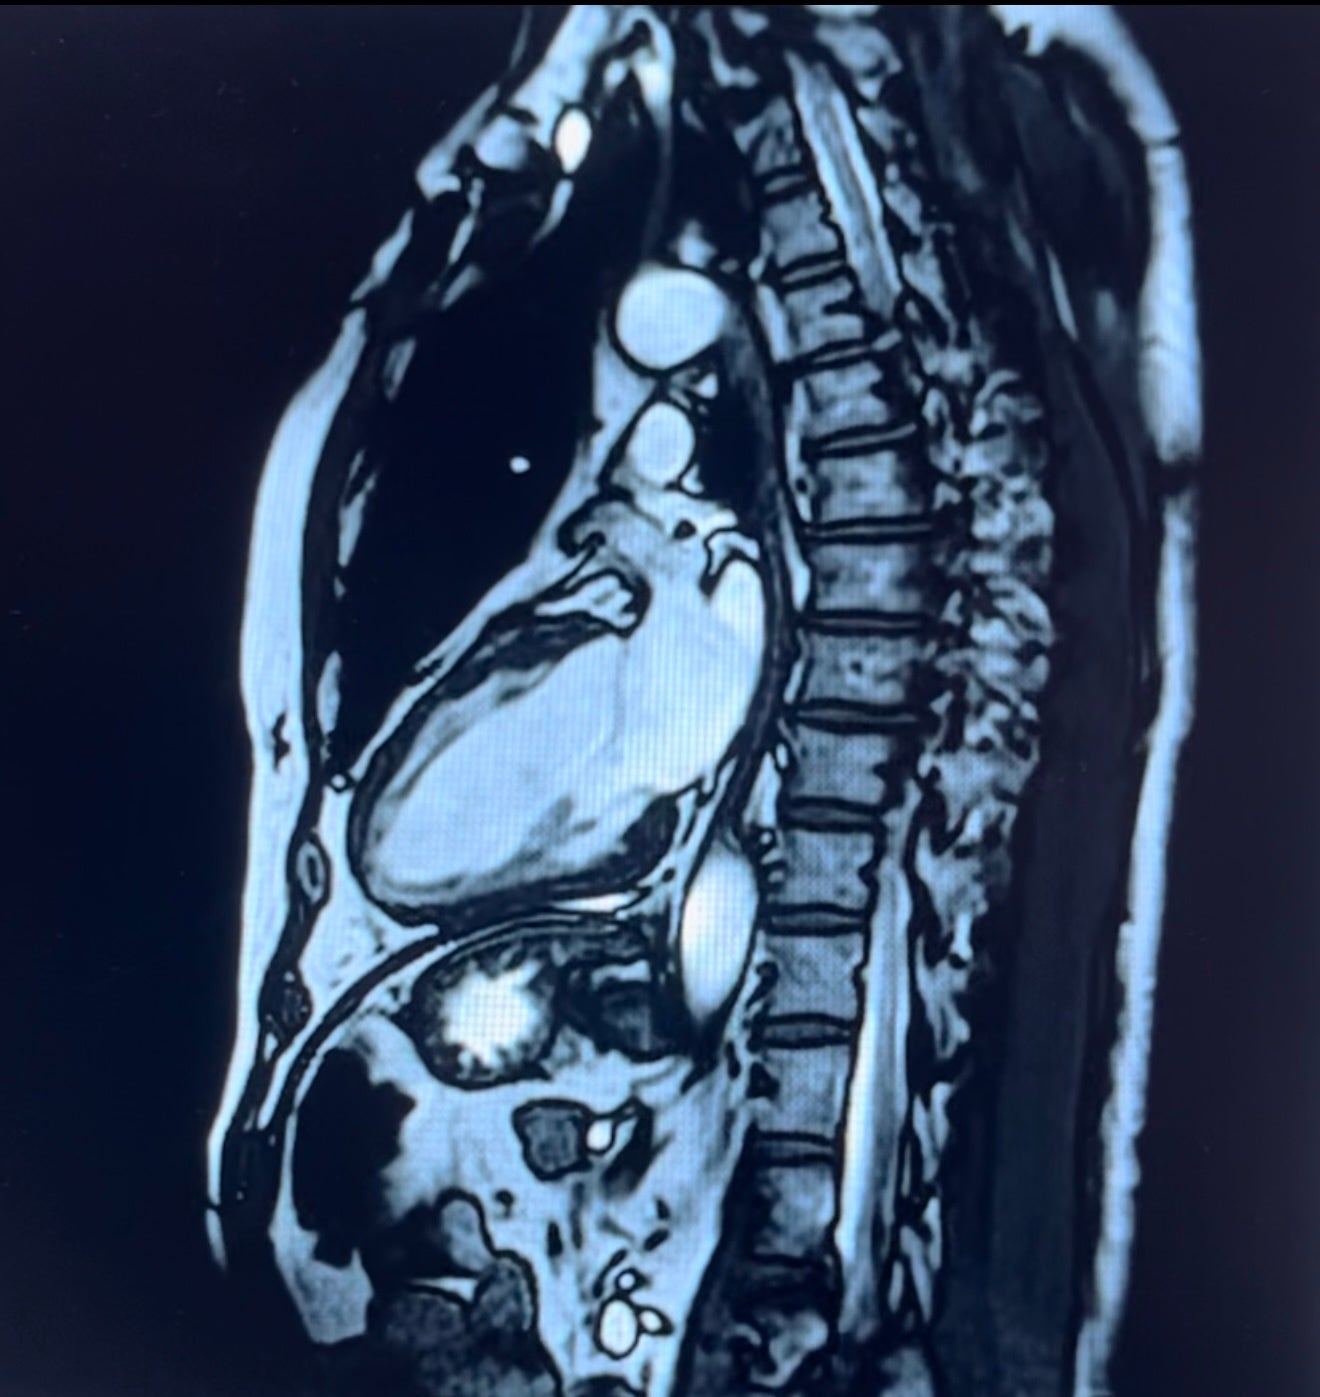

・心臓MRI

放射線を被爆することなく、心臓機能解析が複数断面で定量的に行えるようになり、三次元の動画と

して描出することが可能です。

心臓MRI画像